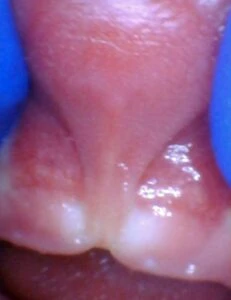

Spectrum of lip restriction in an infant

Spectrum of tongue restriction in an infant

Posterior tongue-tie in an infant seen with lifting the tongue. The posterior or “hidden”tongue-tie can cause the same symptoms including nursing pain and poor weight gain, as a to-the-tip tie in an infant